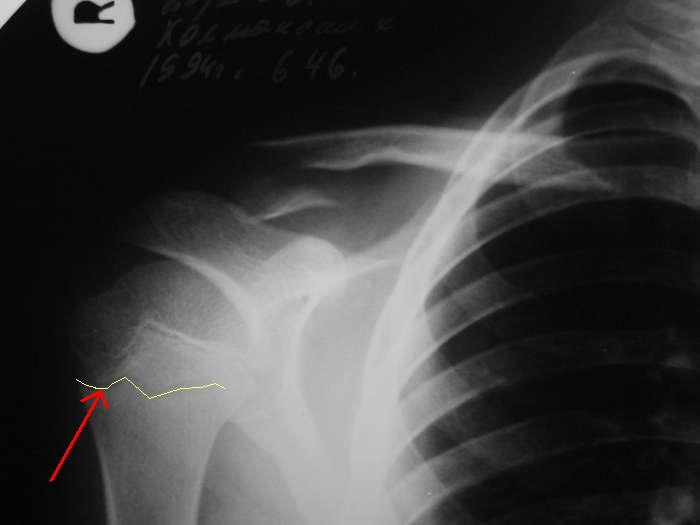

Александр, простите за настойчивость, на картинке я указал смутившую меня тень ... это вариант зоны роста?

> Александр, простите за настойчивость, на картинке я указал

> смутившую меня тень ... это вариант зоны роста?

Это контур зона роста на передней поверхности кости.